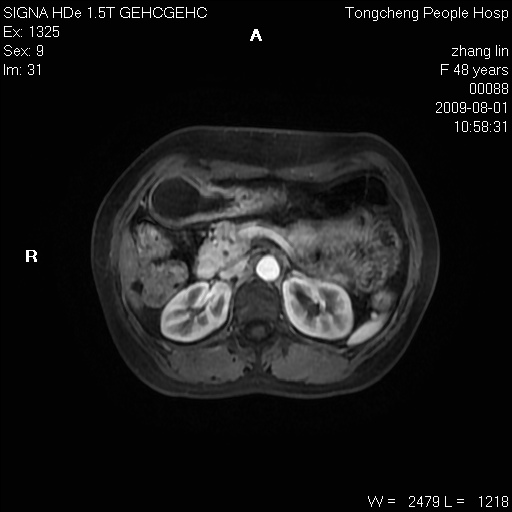

女,48岁。健康体检,彩超发现右肾占位性病变。平素健康。

临床诊断:右肾占位性病变,性质待定(囊肿?肿瘤?)。

上中腹部mr平扫+增强扫描,图像如下:

右肾上极见一类圆形病灶,t1wi呈等信号t2wi呈等高混杂信号,三期增强无强化,边界清---考虑囊肿出血。

同反相位均表现为等信号,病变无强化,考虑含蛋白的囊肿可能,弥散加权相或许有些帮助,